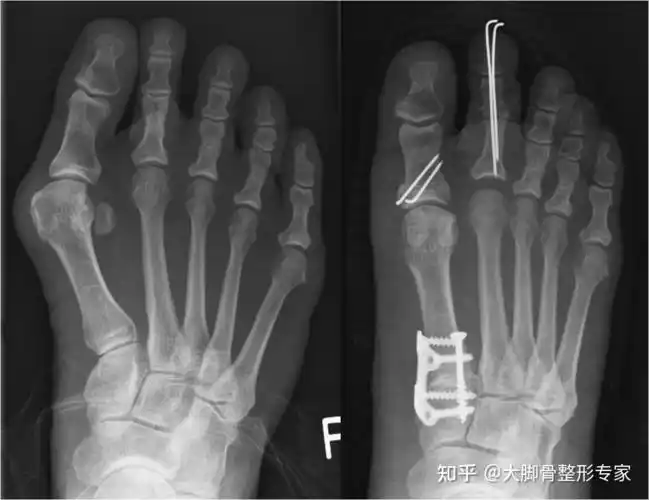

微创手术治疗拇外翻,医保报销,费用低,术后即可下地

脚骨x光片术前术后对比在油管上查了很多关于拇外翻手术的视频(血腥

做大脚骨手术一定要上钢板吗微创效果佳恢复快